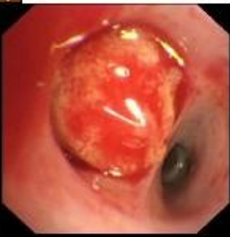

患者入院当日停吗替麦考酚酯、他克莫司,强的松减量至10 mg每日1次口服,隔日血液透析,送检血液mNGS,次日报告:马尔尼菲蓝状菌(序列数4 794)、人类疱疹病毒5型(序列数42)(入院10日后血培养、中段尿培养报马尔尼菲蓝状菌,痰培养、痰浓缩集菌抗酸菌检测阴性)。查血液真菌G试验28.82 pg/mL,GM试验2.59,血液INF-γ释放试验阴性。予莫西沙星0.4 g每日1次静滴、伏立康唑0.2 g每日2次静滴、两性霉素B脂质体(峰克松)逐步加量至50 mg每日1次静滴联合抗感染,监测伏立康唑血药谷浓度3.53 μg/mL,17 d后停两性霉素B脂质体。期间双眼结膜红肿充血加重,伴不自主流泪,右鼻翼、鼻腔、左侧嘴角处溃疡扩大,先后加用妥布霉素滴眼液、卡波姆滴眼液、金霉素眼膏、莫匹罗星软膏外涂。入院19 d后仍有间断发热,CRP升至44.6 mg/L,PCT升至4.32 μg/L,复查CT左肺上叶见类圆形及斑片状密度增高影较前增大,右肺下叶叶间裂处可见多发斑片状密度增高影(图 2B)。行支气管镜检查,术中左舌叶上侧支一亚支可见球型新生物堵塞管腔,表面粗糙,触之易出血(图 3),病理活检示组织急慢性炎症,局部见大量泡沫样组织细胞反应,抗酸染色未发现阳性菌(图 4)。肺泡灌洗液(BALF)GM试验0.84,BALF mNGS报烟曲霉(序列数11),马尔尼菲蓝状菌(序列数5),哥伦比亚分枝杆菌(序列数4989),人类疱疹病毒5型(序列数162),人类疱疹病毒4型(序列数6)。痰液及BALF分枝杆菌培养均阴性。明确诊断为“⑴播散性马尔尼菲蓝状菌病;⑵肺非结核分枝杆菌病(哥伦比亚分枝杆菌);⑶侵袭性肺曲霉菌病(烟曲霉)”。考虑利福平显著影响伏立康唑血药浓度,未加用利福平。抗感染方案调整为伏立康唑0.2 g每日2次静滴、乙胺丁醇0.75 g每日1次口服、阿奇霉素0.5 g每日1次口服、利奈唑胺0.6 g每日2次静滴。患者静滴利奈唑胺期间出现胸闷、恶心,停利奈唑胺,恢复莫西沙星0.4 g每日1次静滴,监测体温峰值逐步下降,出院1周前未再发热。在院43 d,出院前CRP 1.1 mg/L,PCT 0.342 μg/L,血液真菌G试验9.9 pg/mL,GM试验0.22,CD4+T 143个/uL,双侧眼睑红肿好转,右侧鼻翼、鼻腔及左侧嘴角溃疡消退(图 1b)。复查CT左肺上叶、右肺下叶叶间裂处仍见高密度影(图 2C)。患者出院后继续口服伏立康唑、阿奇霉素、乙胺丁醇、莫西沙星抗感染,期间未再发热,常规血液透析治疗,3个月后复查CD4+T 314个/uL,CT左肺上叶团块影和右肺下叶叶间裂结节体积较前明显缩小(图 2D)。

| 图 3 支气管镜可见左上肺球型新生物堵塞管腔 |